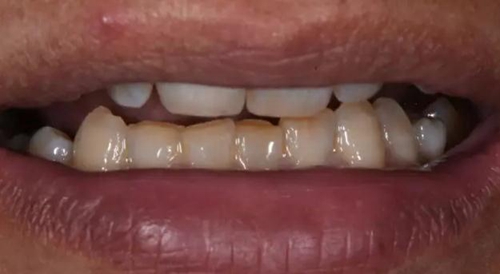

術(shù)后口內(nèi)照片

修復(fù)體戴入口內(nèi)后照片,與鄰牙鄰接良好。